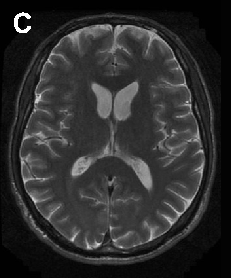

In ChAc and MLS, electroneurography may demonstrate sensorimotor axonal neuropathy whereas electromyography may show neurogenic as well as myopathic alterations. Electroencephalographic findings are not specific and may comprise normal findings, generalized slowing, focal slowing, and epileptiform discharges. Neuroradiologically, there is progressive striatal atrophy especially affecting the head of caudate nucleus and impaired striatal glucose metabolism similar to that seen in HD (Figure 2) [24,26]. Voxel-based morphometry of MRI scans in ChAc shows specific involvement of the head of the caudate nucleus [41,42]. Neurodegeneration in both core NA syndromes affects predominantly the caudate nucleus, putamen and globus pallidus. In ChAc, thalamus and substantia nigra are also involved. In contrast to HD, there is no significant cortical pathology [8,43-45]. Neuropathological findings consist of neuronal loss and gliosis of variable degree in these regions, but no inclusion bodies of any nature or other distinct neuropathological features have as yet been detected.

Cerebral MRI is often diagnostic in PKAN, and the diagnosis is confirmed by analysis of the PANK2 gene (Figure 2). Analysis of the JPH3 gene CTG expansion is useful in patients of African ancestry with suspected HDL2.

A B

C D

E F

G H

Figure 2 Neuroimaging. ChAc. Coronal FLAIR- (A) and axial T1-weighted (B) images demonstrate moderate atrophy of the caudate nucleus. MLS. Axial T2-weighted images demonstrate moderate atrophy of caudate nucleus and putamen (C) but no relevant cortical atrophy (D). HDL2. Axial FLAIR- (E) and coronal T1-weighted images (F) demonstrate atrophy of the caudate nucleus and the fronto-temporal cortex. In addition, FLAIR images show periventricular white matter hyperintensities (courtesy of Nora Chan, MD, UCLA, Los Angeles, USA). PKAN. T2-weighted fast spin echo (G) and T1-weighted (H) brain MRI scans from a child with PKAN demonstrating the “eye of the tiger” sign (courtesy of Susan J. Hayflick, MD, Oregon Health and Science University, Portland, Oregon, USA)